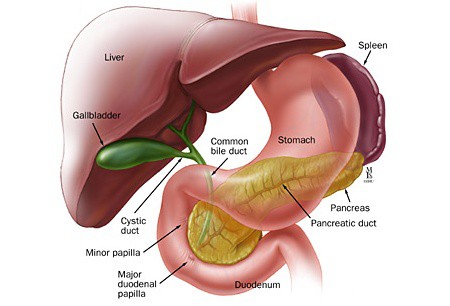

The liver is located in the upper right-hand portion of the abdominal cavity, beneath the diaphragm, and on top of the stomach, right kidney, and intestines

The gallbladder is a small organ located just below your liver in your right upper abdomen. It stores bile, which is a liquid produced in the liver. The gallbladder releases bile into the small bowel to help break down and absorb dietary fats. Normal digestion is possible without a gallbladder.

Multiple worms in CBD are well known, and ultrasound is considered a very useful modality for diagnosis and for follow-up. Also, there can be worms in bile ductules that may lead to the persistence of symptoms despite of CBD clearance. Follow-up ultrasound is thus mandatory if symptoms persist.

Pancreatic cancer begins in the tissues of your pancreas — an organ in your abdomen that lies behind the lower part of your stomach. Your pancreas releases enzymes that aid digestion and produces hormones that help manage your blood sugar.